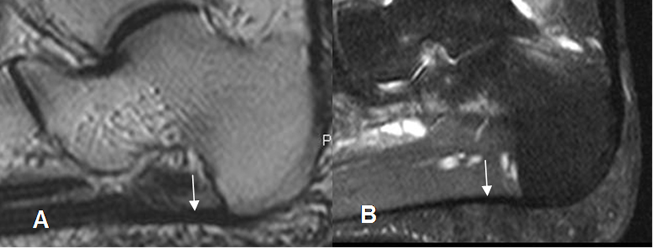

Fig 23. Tendón de aquiles normal.

A: Ecografía transversa y B: RM axial en T1. Estructura ovalada y homogénea, cóncava anteriormente. En RM hay zonas hiperintensas, que corresponden a septos.

Fig 24. Tendón de aquiles normal.

RM sagital en T1. Estructura lineal e hipointensa en todas las secuencias.